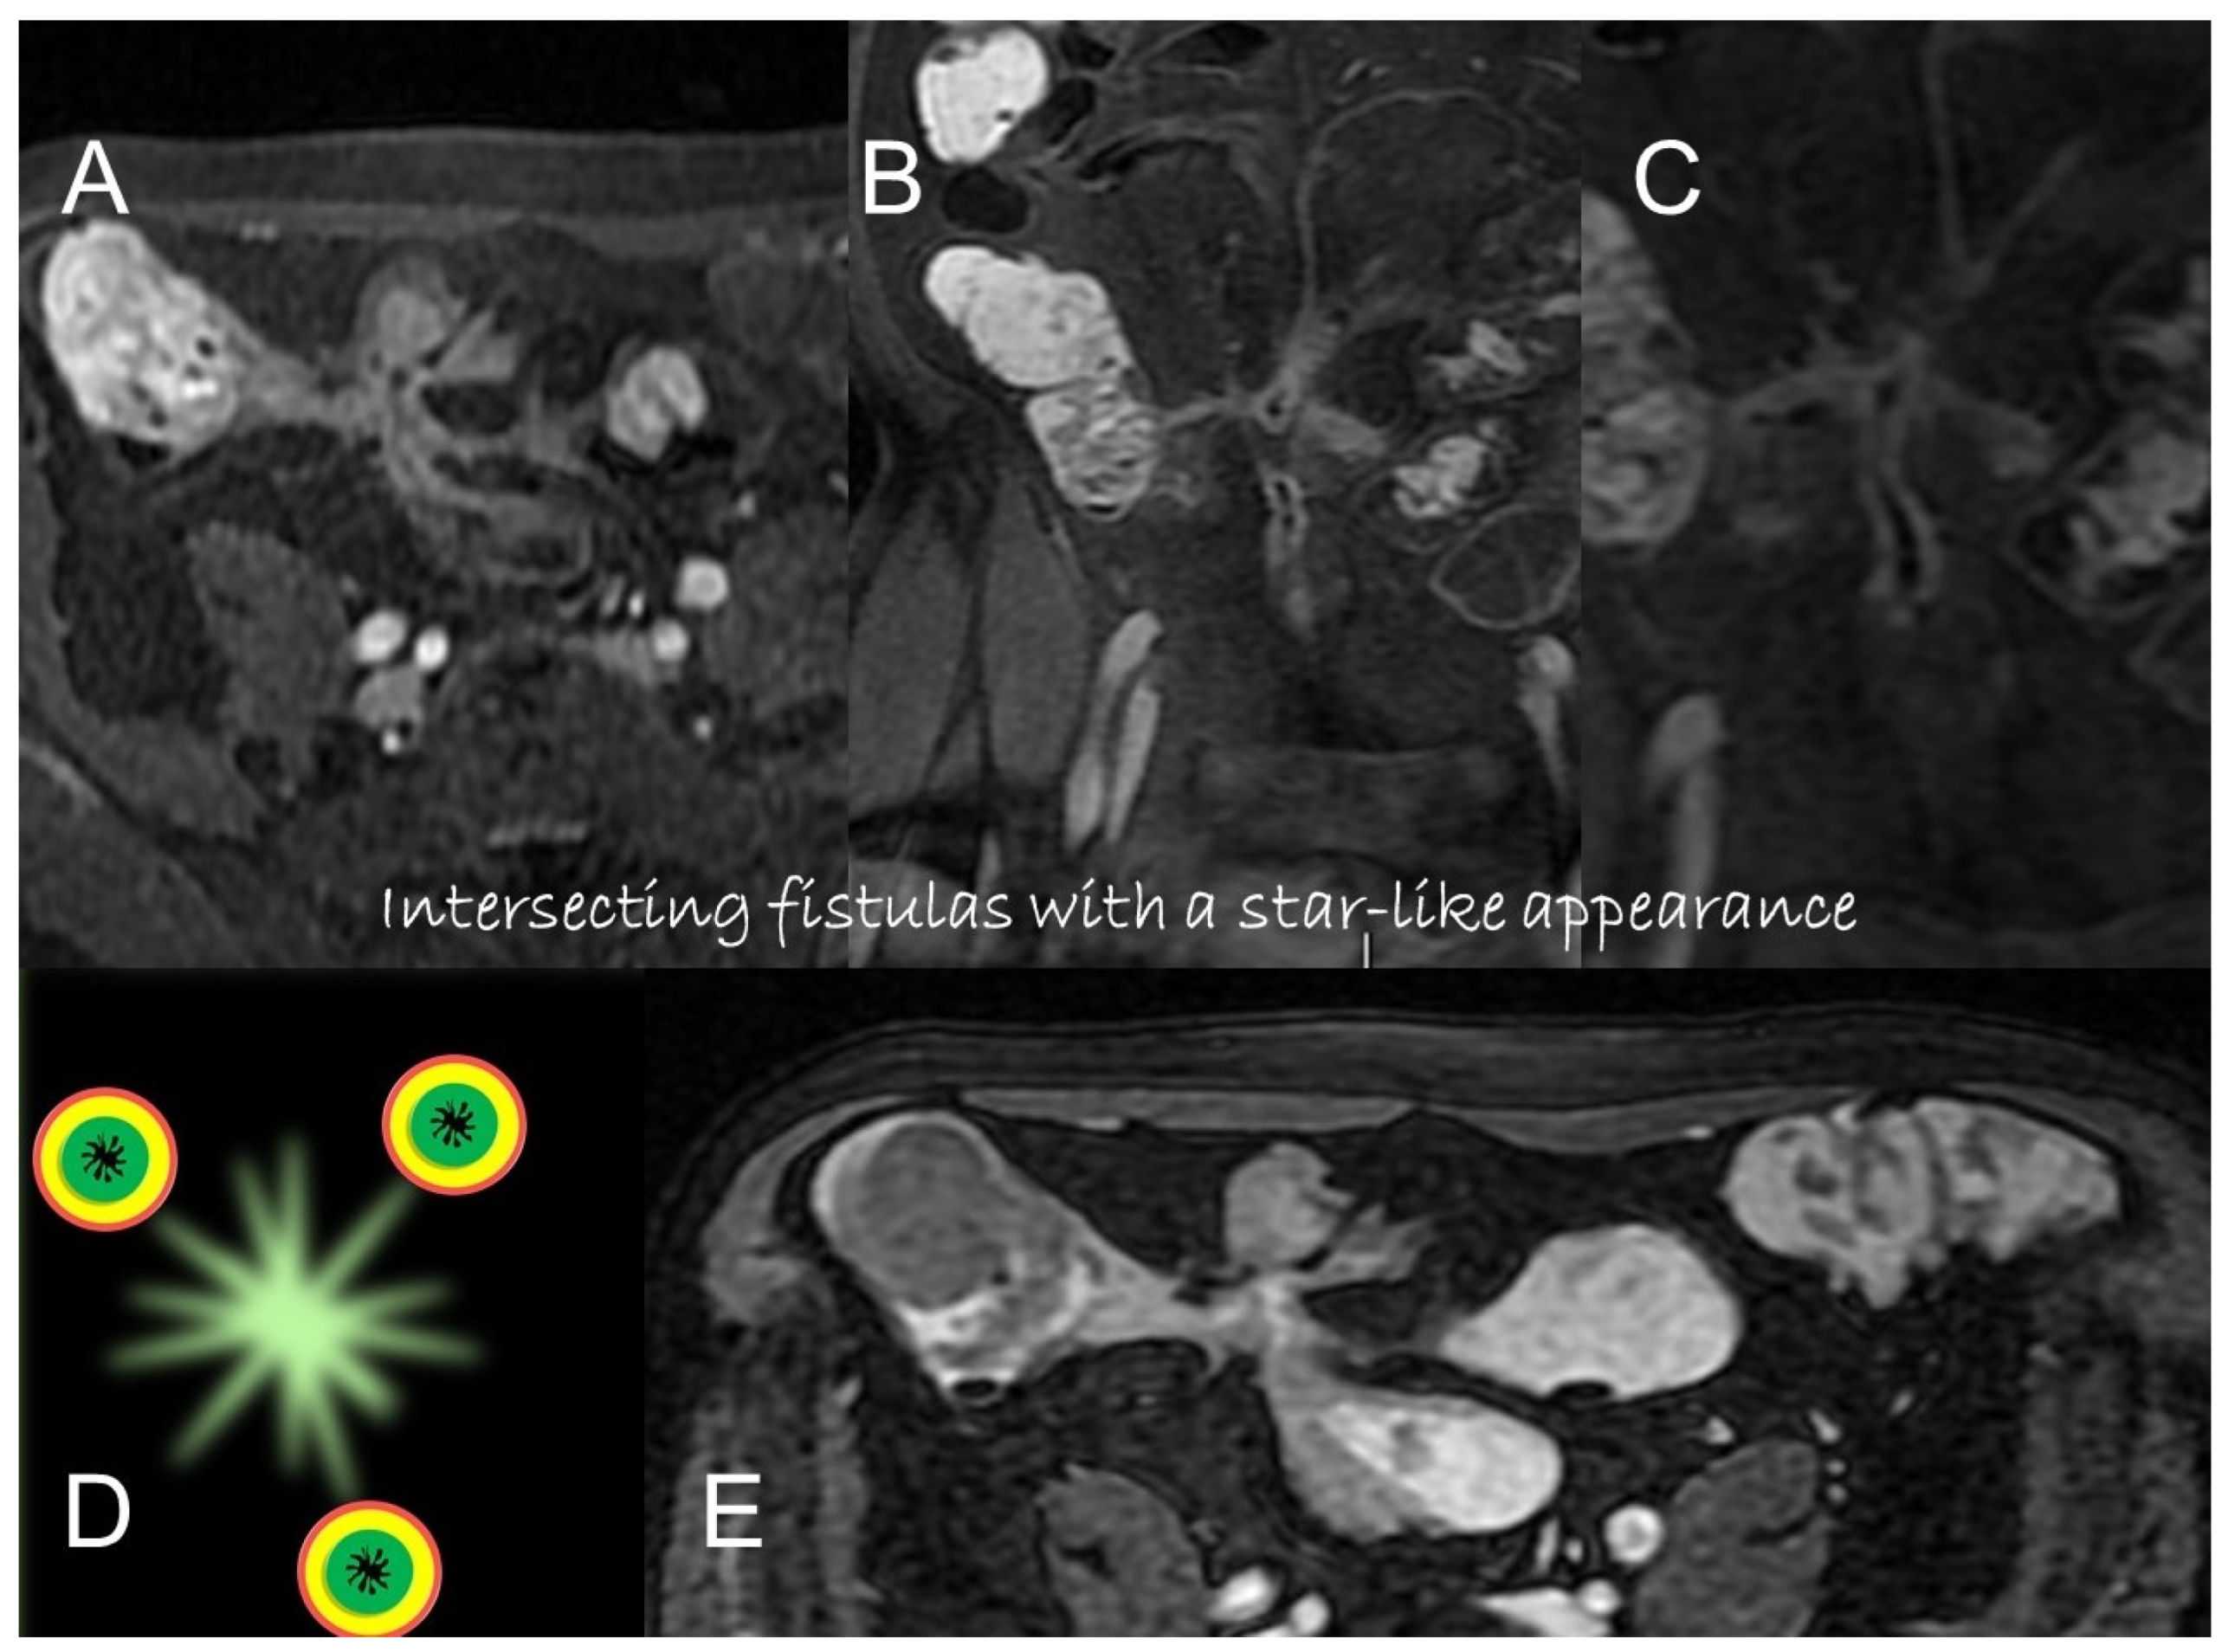

Unlike the sinus tracts, a fistula is defined as a pathologic channel connecting two or more epithelialized surfaces [11]. Fistulae can be simple (single extra enteric tract: enter enteric, enter colic, enter vesical, enterocutaneous, or rectovaginal) or complex (branching and intersecting fistulas, sometimes with a star-like appearance [5]). They represent a complication in approximately 14–50% of the patients with Crohn’s disease (Figure 9, Figure 10 and Figure 11).

Figure 10.

Axial (A) and coronal (B,C) contrast-enhanced fat-suppressed T1-weighted images and axial FIESTA image (E) of the same patient show a complex fistula formed by the intersection of multiple fistulous arms that connect pathological segments of the small intestine to each other and to the ascending colon through the mesentery. These fistulous pathways, intersecting each other, end up taking on the starry appearance, typical of complex fistulas (D).